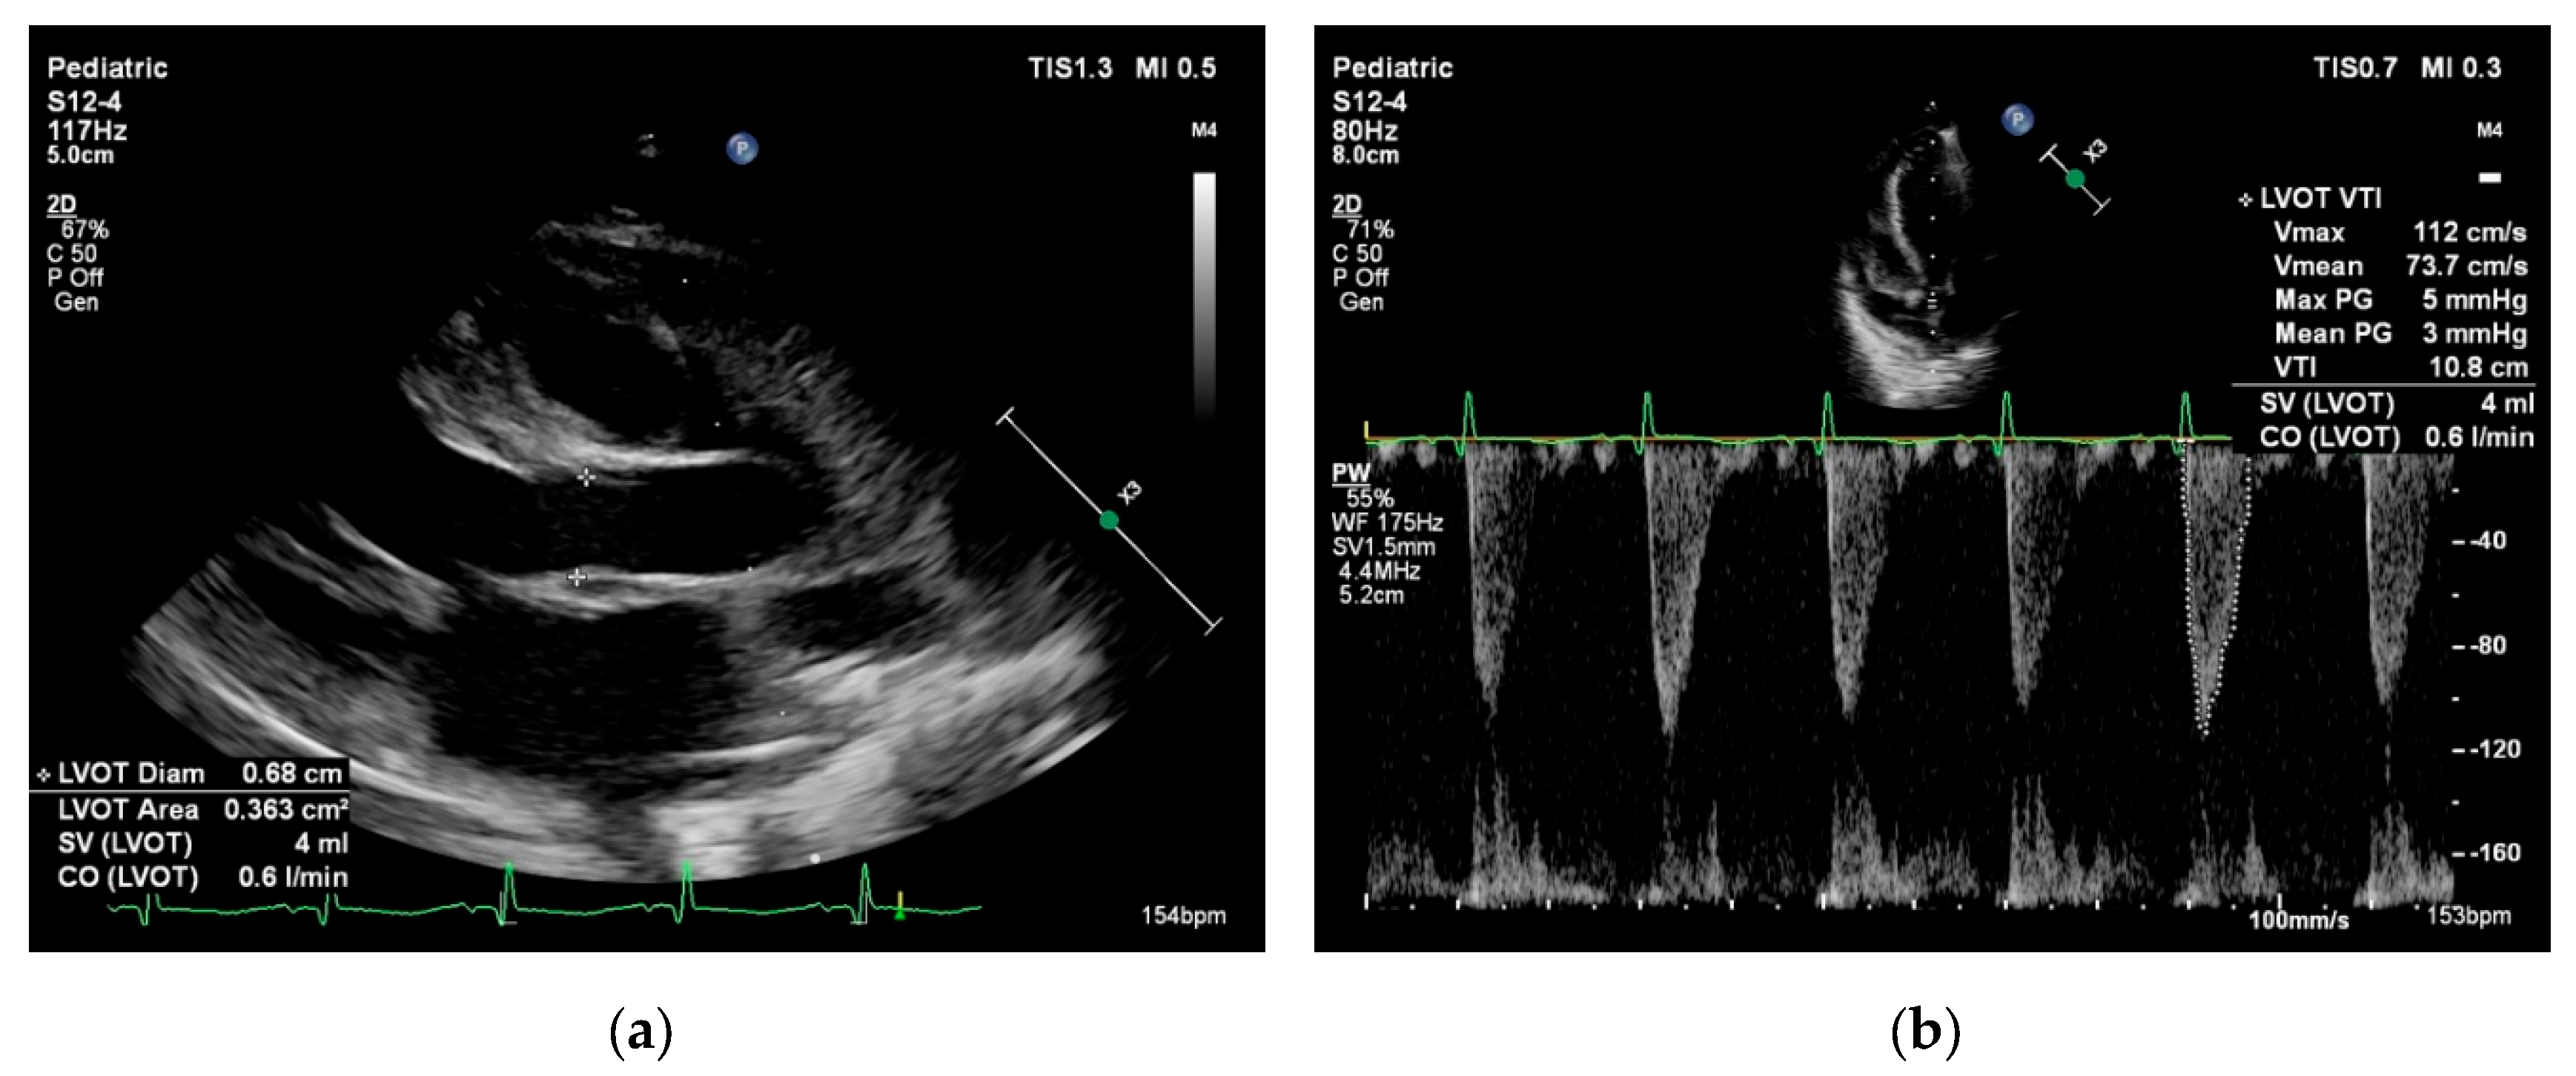

Systemic blood flow (left ventricular output, LVO) and pulmonary blood flow (right ventricular output, RVO) can be estimated by calculating the product of the Doppler flow velocity (velocity time integral, VTI), the cross-sectional area (CSA) of the left or right ventricular outflow tracts, and heart rate. In the presence of intra- or extracardiac shunts, LVO and RVO are not interchangeable. There are normative data for neonatal VTI and cardiac index, but these measurements are highly dependent on correct ultrasound probe positioning and accurate estimation of the outflow tract diameter (see Figure 2) [52].

Figure 2. Cardiac output measurement performed in the parasternal long axis view in a neonate with miocarditis admitted to the Neonatal Intensive Care Unit at the “Maria Sklodowska Curie” Emergency Clinical Hospital for Children. Cardiac output = stroke volume x heart rate. Stroke volume = velocity time integral × cross sectional area. (a) Left ventricle outflow tract (LVOT) cross sectional area = π × (LVOT diameter/2)2; (b) Velocity time integral is measured using pulsed wave Doppler at the level of the LVOT.